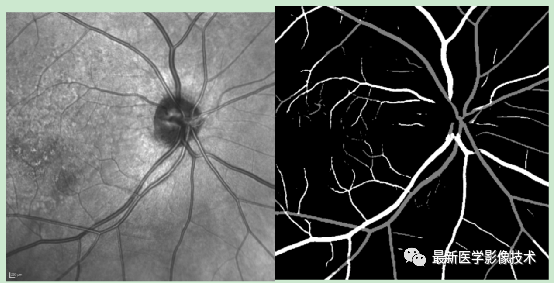

4、验证集分割结果,左图是眼底图像,中间是金标准图像,右图是分割图像

5、测试集部分分割结果